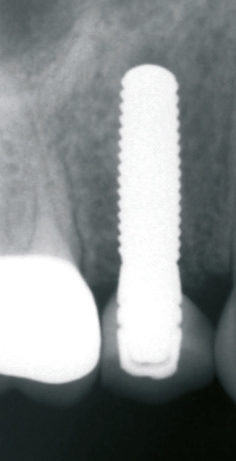

Implantatinsertion

Nach sorgfältiger Kürettage und Inspektion einer idealen Knochenalveole vom Typ I [11] konnte mit der Sofortimplantation begonnen werden. Die ersten beiden Pilotbohrungen wurden teilnavigiert mit der Bohrschablone durchgeführt. Das restliche Bohrprotokoll wurde nach den Vorgaben des Herstellers frei durchgeführt. Mit der Insertion des Implantats konnte die nötige Primärstabilität von 35 Ncm für eine sofortige provisorische Versorgung erreicht werden. Im Vorfeld war ein Situationsmodell der Ausgangssituation und darauf eine Tiefziehschiene vorbereitet worden, die jetzt für die intraorale Herstellung des Provisoriums mit fließfähigem Kompositmaterial verwendet wurde. Als stabilisierende Gerüststruktur diente dabei die präzise sitzende Einbringkappe (insertion.transfer) auf dem Implantatkopf, die zuvor auf die entsprechende Höhe eingekürzt worden war. Nach der Ausarbeitung und okklusalen Adjustierung der Krone wurde diese provisorisch zementiert.

Nach einer komplikationsfreien Einheilzeit von vier Monaten konnte mit der Herstellung des definitiven Zahnersatzes begonnen werden. Hier entschied man sich konsequent für monolithische Kronen aus Lithiumdisilikat, um das Chippingrisiko so gering wie möglich zu halten [12]. Im Zuge der Implantatversorgung wurde nun auch – wie geplant – die metallkeramische Krone an 16 geschlitzt, entfernt und der Stumpf nachpräpariert. Implantatkopf und Zahnstumpf wurden daraufhin zusammen mit A-Silikon analog abgeformt. Für die geschlossene Abformung wurde die Abformkappe (impression.transfer) auf dem Implantatkopf positioniert. Ein deutliches Einrasten signalisierte den lagestabilen Sitz. Für die Modellherstellung rastete das Implantatanalog (lab. replica) ebenso in die integrierte Abformkappe ein. Nach der Herstellung des Meistermodells konnten die beiden Kronen im digitalen Workflow CAD/ CAM-gestützt gefertigt werden. Nach Ausarbeitung, Bemalung und Glasur waren die beiden Kronen für die definitive Zementierung bereit. Die klinische Einprobe der Restaurationen verlief erfolgreich, sodass die Kronen nacheinander mit selbstadhäsivem Befestigungskomposit eingegliedert werden konnten.